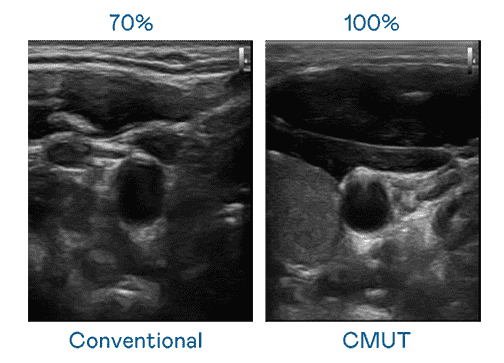

CMUT 技术是一种用电容式微机电元件来产生超音波讯号的技术。。与传统 PZT 压电式技术相比,,CMUT 频宽增加 30%,,更宽频的超音波讯号让影像解析度大幅提升,,是实现高影像品质医疗超音波扫描、、、促进精准医疗发展的关键技术。。。。

大频宽带来超清晰影像

超音波影像的解析度高低,,,首先取决于探头能发出的讯号频宽。。。。PA直营 CMUT 可提供高清晰的超音波讯号,,,提供高频宽、、、高灵敏度、、、、影像纹理细节更高的超音波影像,,,,协助医护人员缩短影像判读时间及利用精准的医疗影像进行诊断。。。